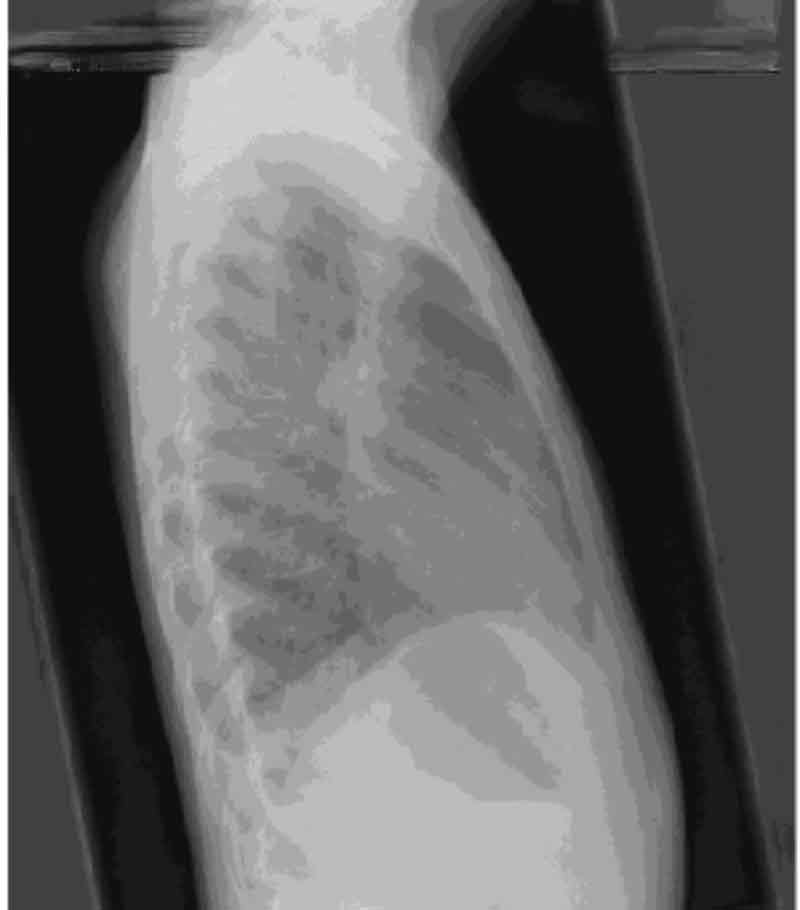

In addition a chest x-ray was ordered. PRESENTED BELOW.

ENLARGE X-ray left, X-ray right.

DO YOU HAVE AN INTERPRETATION OF THE CHEST X-RAY?